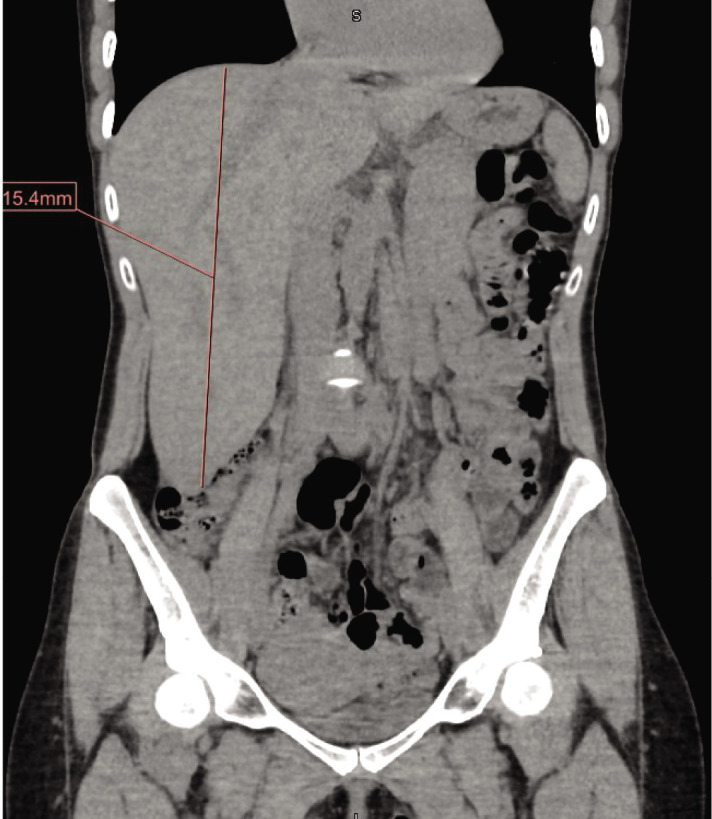

Riedel's lobe of the liver is a rare anatomical variant often incidentally found on imaging or through the presence of hepatomegaly on physical examination. While patients are usually asymptomatic, the presentation of this condition can vary, ranging from nonspecific symptoms to more severe issues such as torsion, obstruction, rupture, and bleeding. We present a case of a patient with asymptomatic hepatomegaly who was incidentally found to have Riedel's lobe of the liver, accompanied by an elevated IgG mitochondrial antibody. The range of symptoms associated with this rare anatomical variation underscores its importance in diagnosis and surveillance within this patient population.

Abstract Image